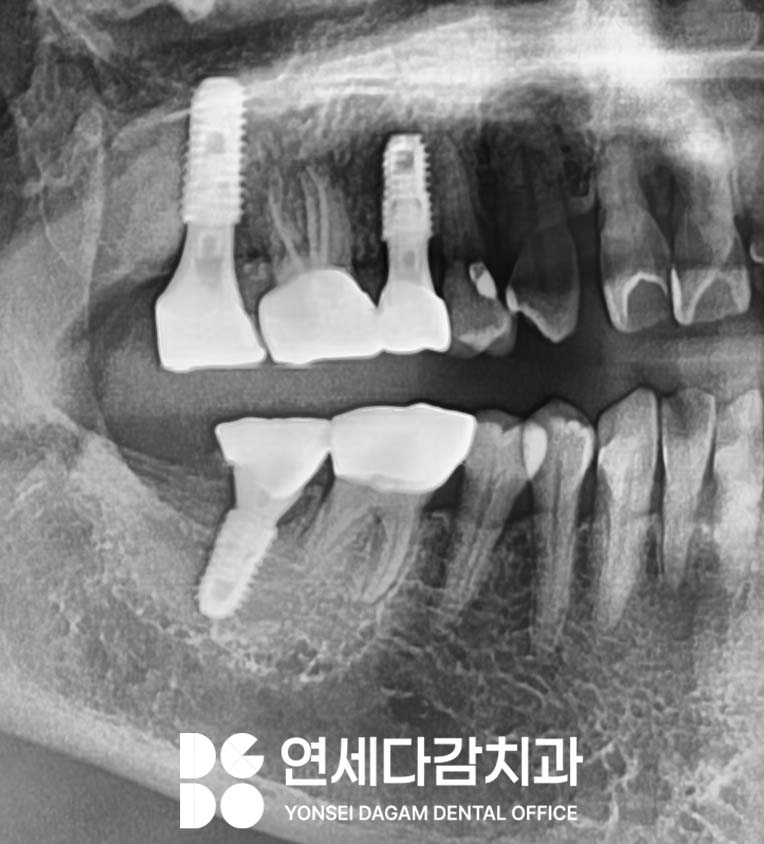

안정적으로 치유되어

최종 보철물도 무사히 완성할 수 있었습니다.

총 3번의 식립 과정을 거치면서

중간중간 뼈가 안정화되는 기간을

가져야 됐기 때문에

전체 치료 기간이 길어질

수밖에 없었습니다.

회복하고자 하는 의지가 강했기에

최종적으로 성공적인 결과를

얻을 수 있었습니다.